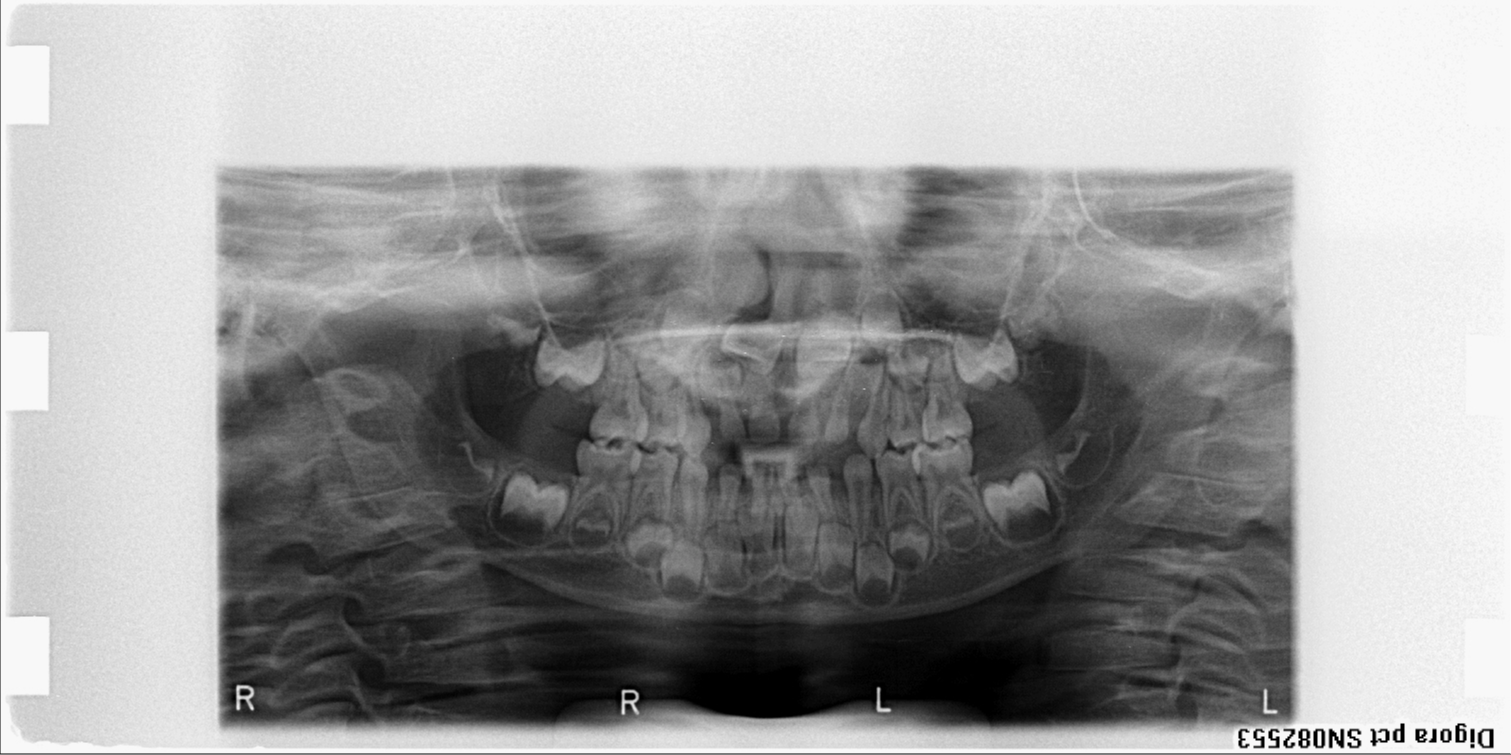

bilan des radiographies début et en cours de traitement